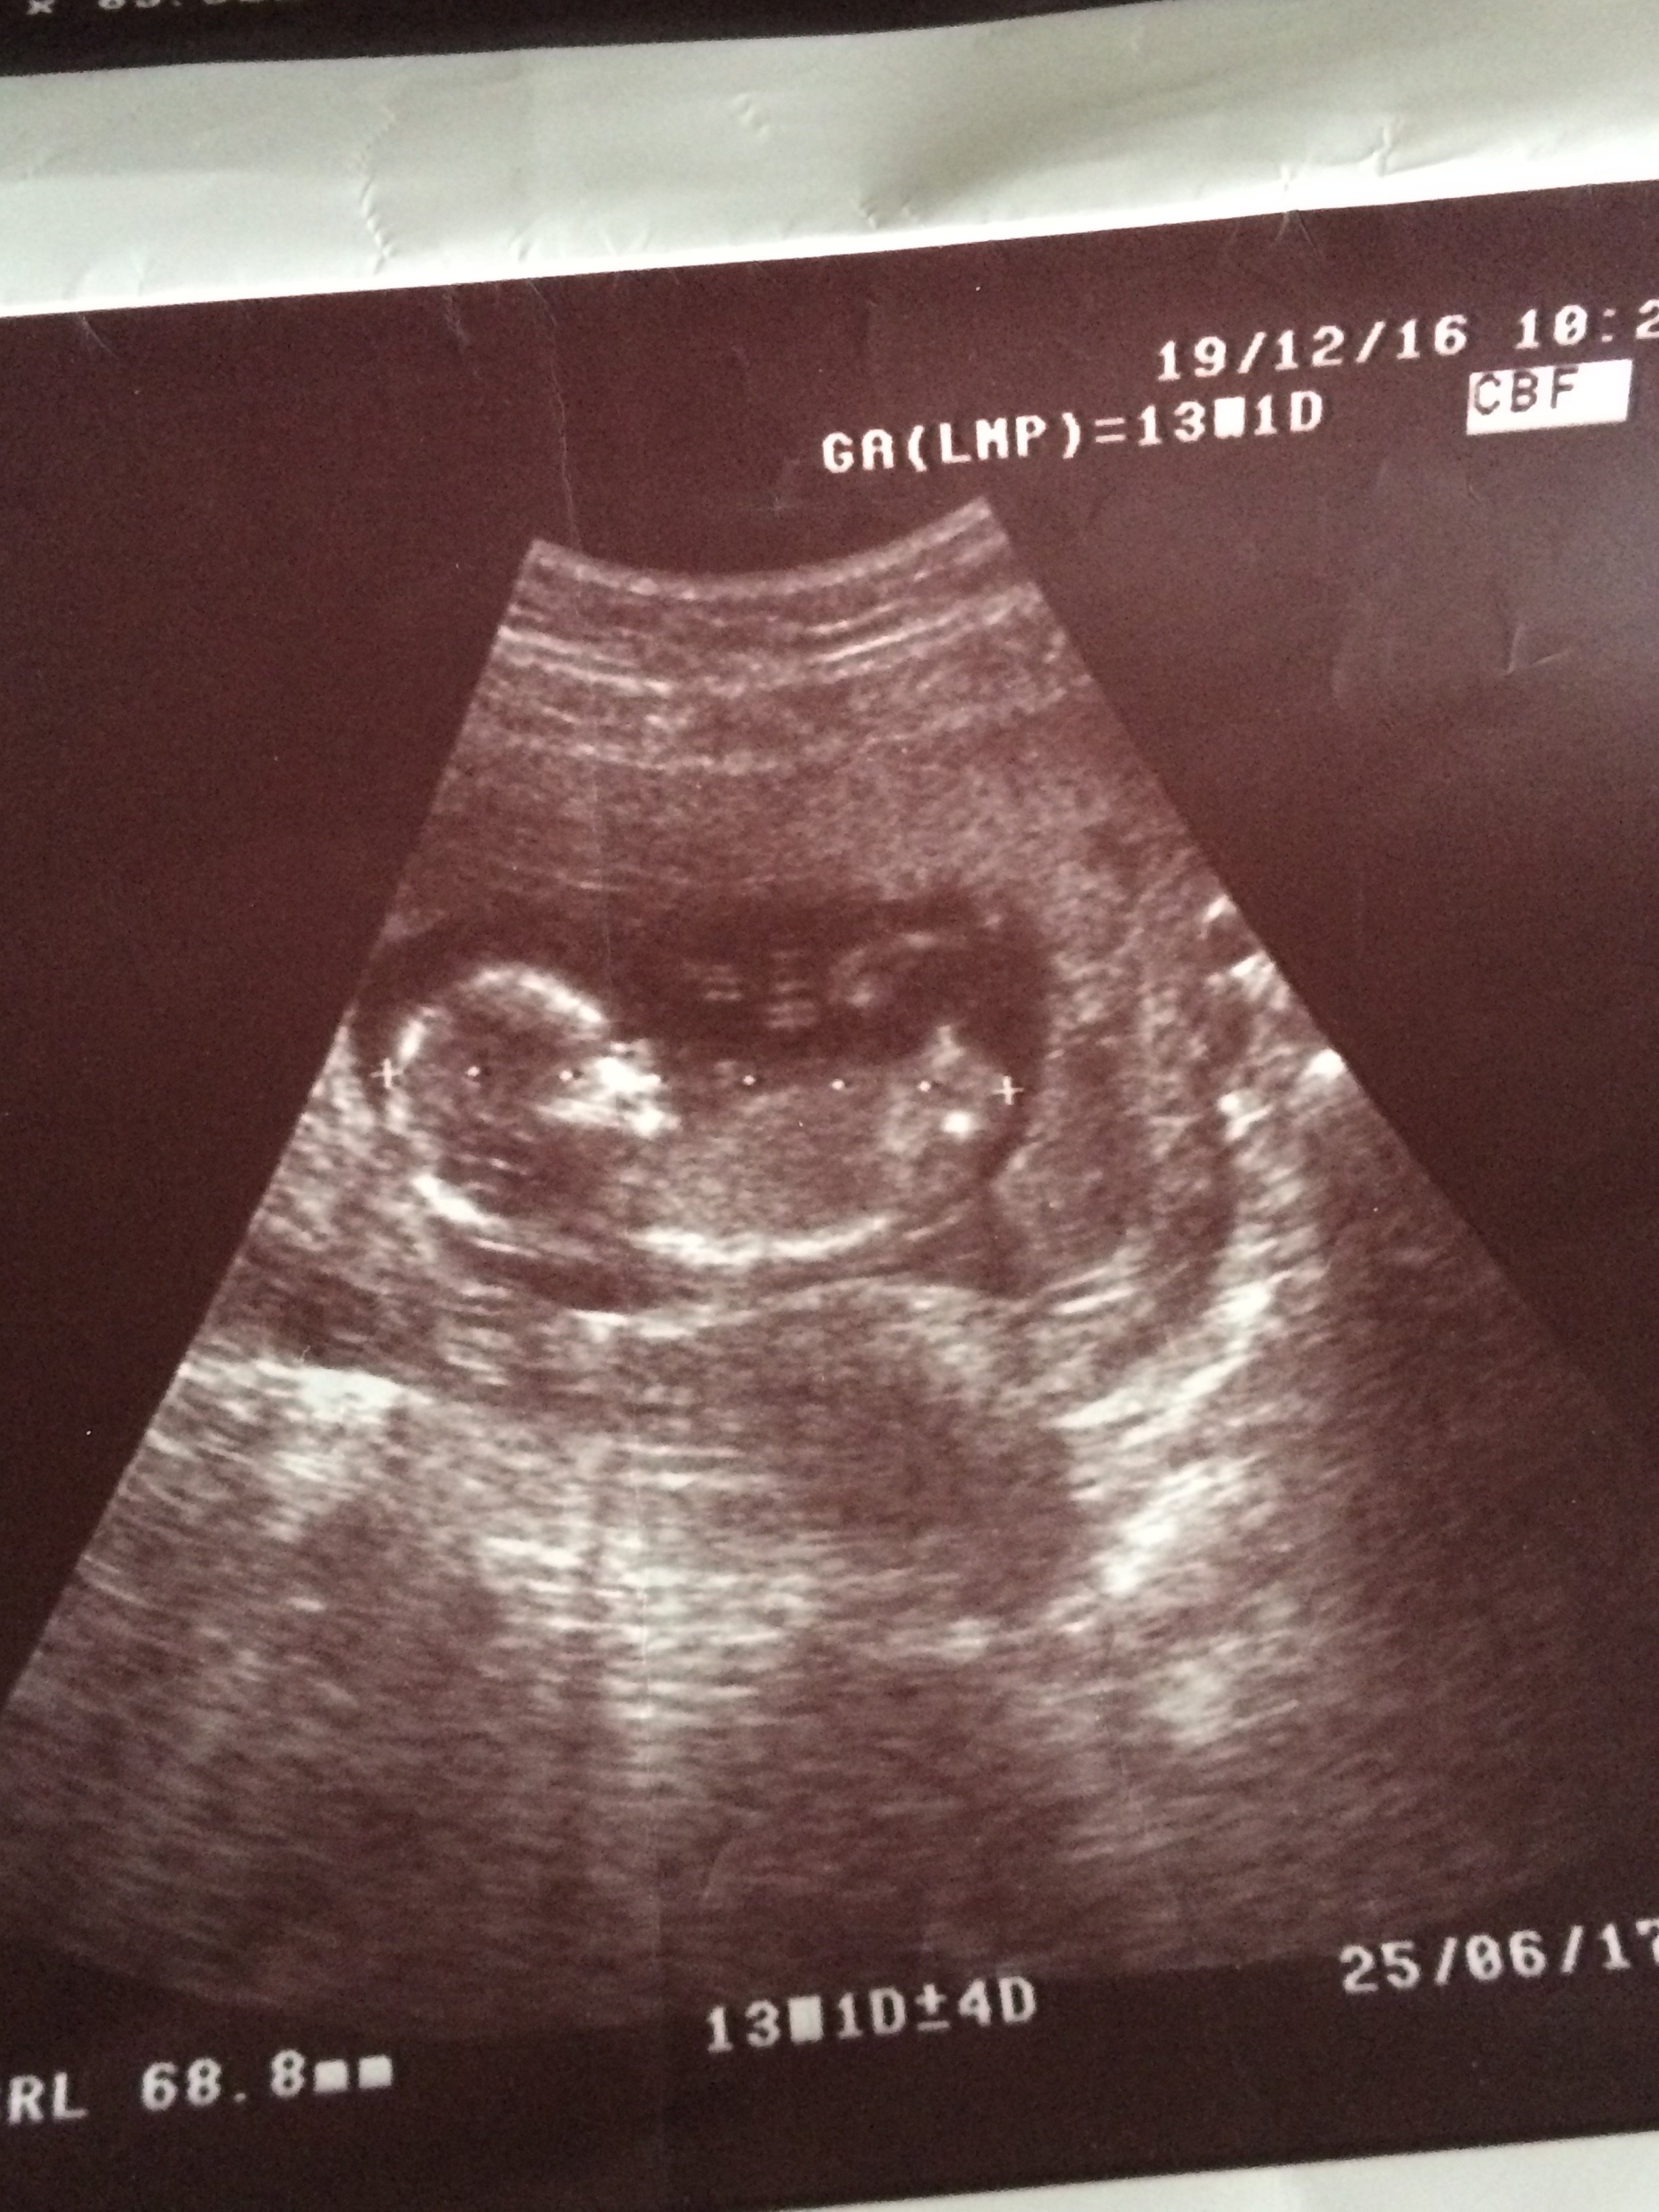

1 1xyz1 Yeni Üye Üye 10 Ocak 2017 #130 Merhaba, fotoğraflardan cinsiyet anlaşılıyor mu? Doktor kız gibi görünüyor dedi. Ekli dosyalar 2.jpg 1,4 MB · Görüntüleme: 608